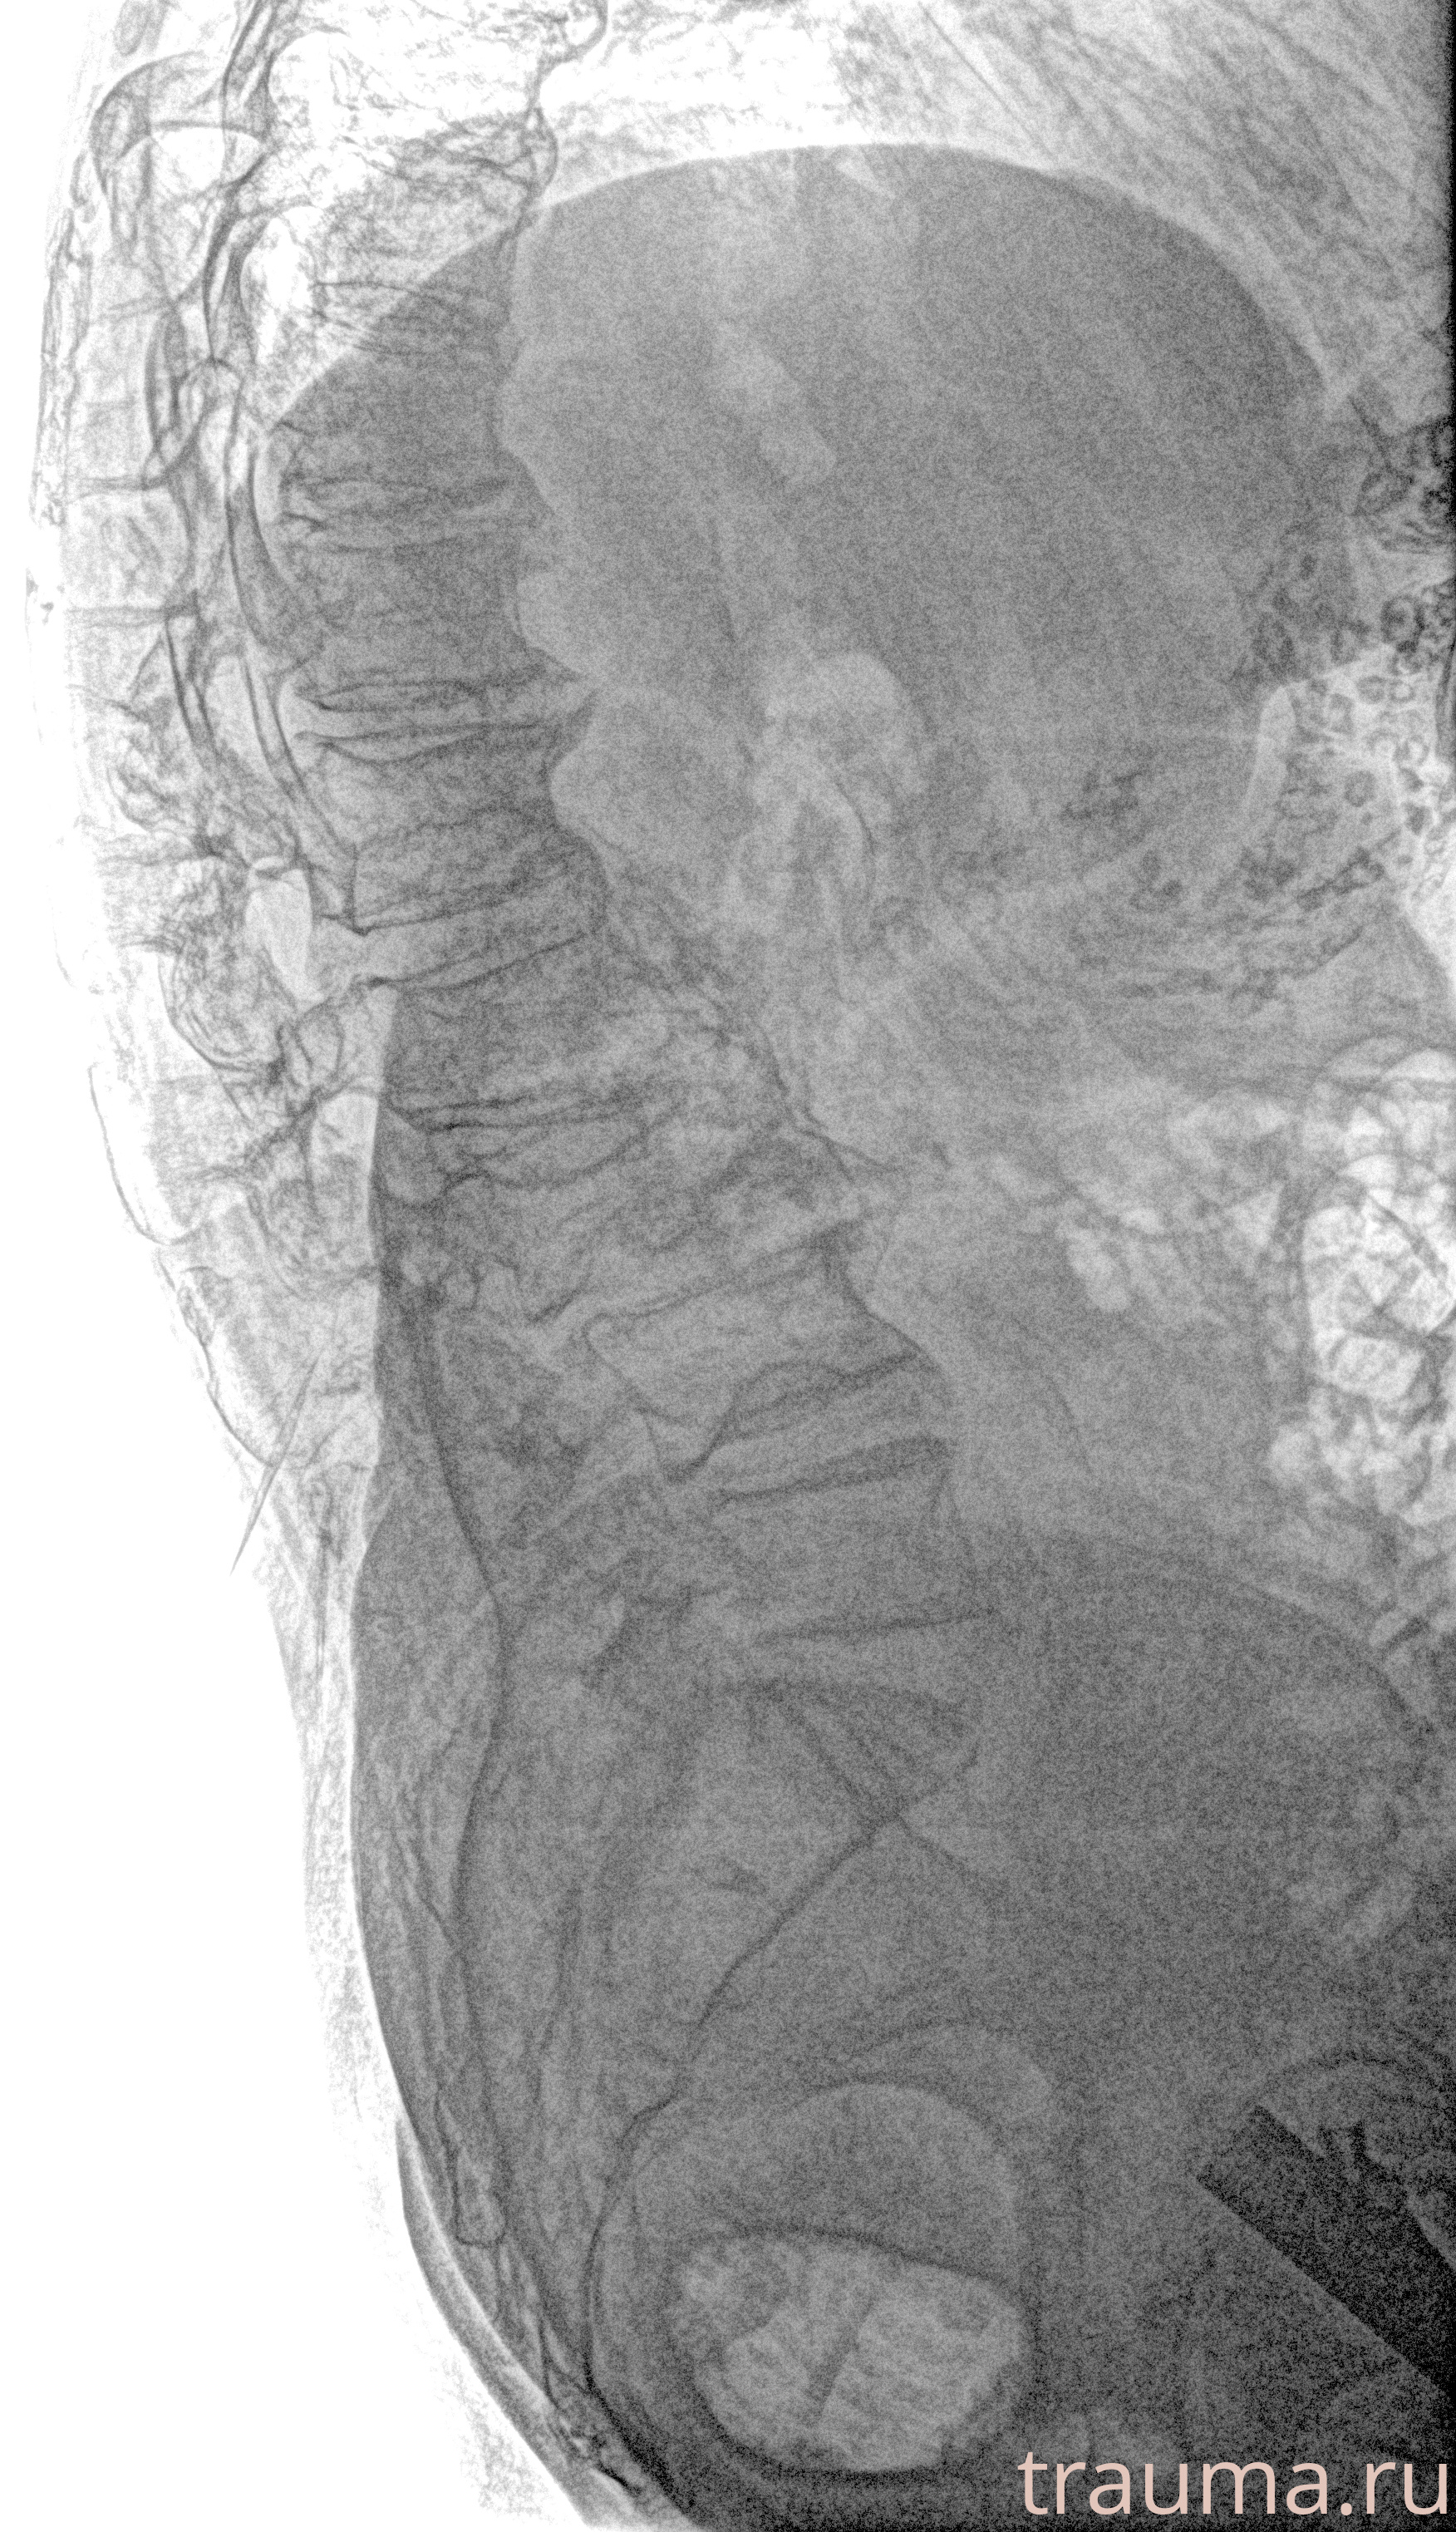

Рентгенограммы

Рентген на дому: по вашему адресу приезжает врач-рентгенолог, травматолог-ортопед с мобильным рентгеновским аппаратом, проводит диагностику травмы или заболевания, делает необходимые рентгенограммы, дает рекомендации по дальнейшему лечению. Получить качественные снимки в домашних условиях возможно благодаря уникальной методике, разработанной МосРентген Центром для института  Склифосовского